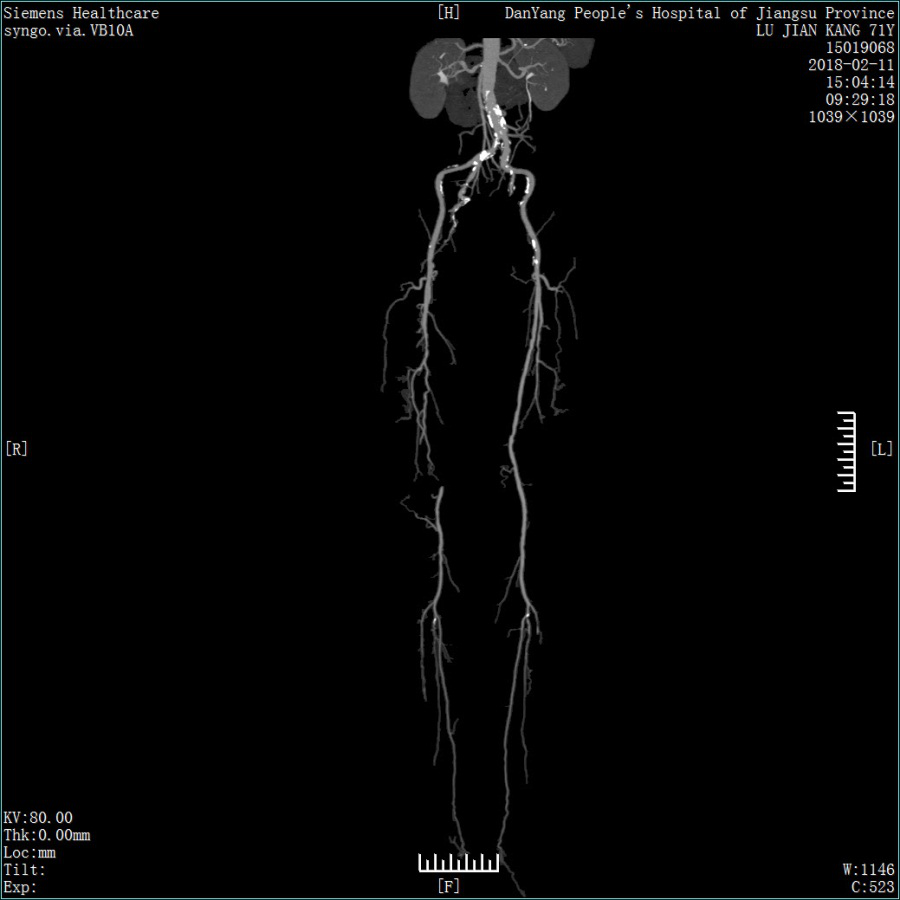

双源CT的检查范围不止

冠心病,还可以测出脑血管、肺动脉、大动脉、肾动脉、四肢动脉、静脉等情况,通过薄层扫描,发现微小的肿瘤,对骨关节、肾结石、胆结石、痛风石等细微的病变都能“明察秋毫”。

4秒全身成像,适合于全身各部位的血管成像及急症病人大范围的扫描。